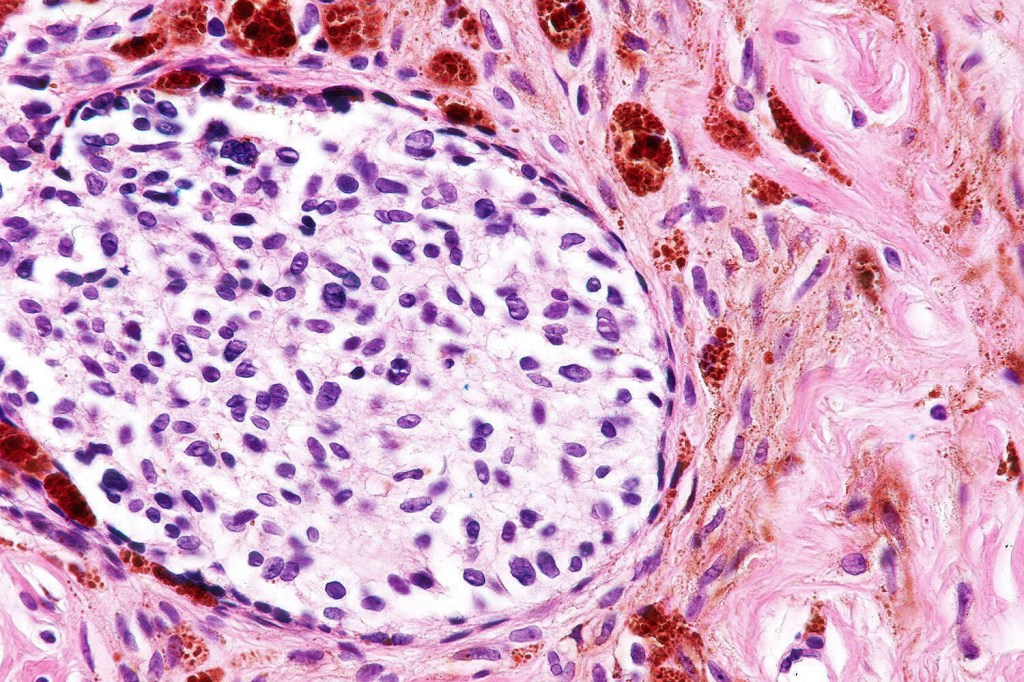

Cellular blue nevus

This uncommon most often devlops on the buttocks, sacrococcygeal region & distal extremities although it may be seen at just about any site. It shows a predilection for females and is diagnosed most often in the 2nd-4th decade. It presents as a blue-black/ or black nodule measuring 1-2 cm in dianeter. Similar to common blue nevus, the cellular variant can be encountered in a wide range of non-cutaneous locations.

Histological features

•Most characteristic is the dumbbell silhouette although a plague morphology may also be encountered

•Admixture of spindle cells, pigmented bipolar or dendritic cells & melanophages

•Cytoplasm is pale and nuclei are small with inconspicuous nucleoli

•An alveolar pattern is characteristic particularly with clear cell nodules

•Stromal fibrosis, myxoid change, vascular hyalinization with cyst formation are often seen